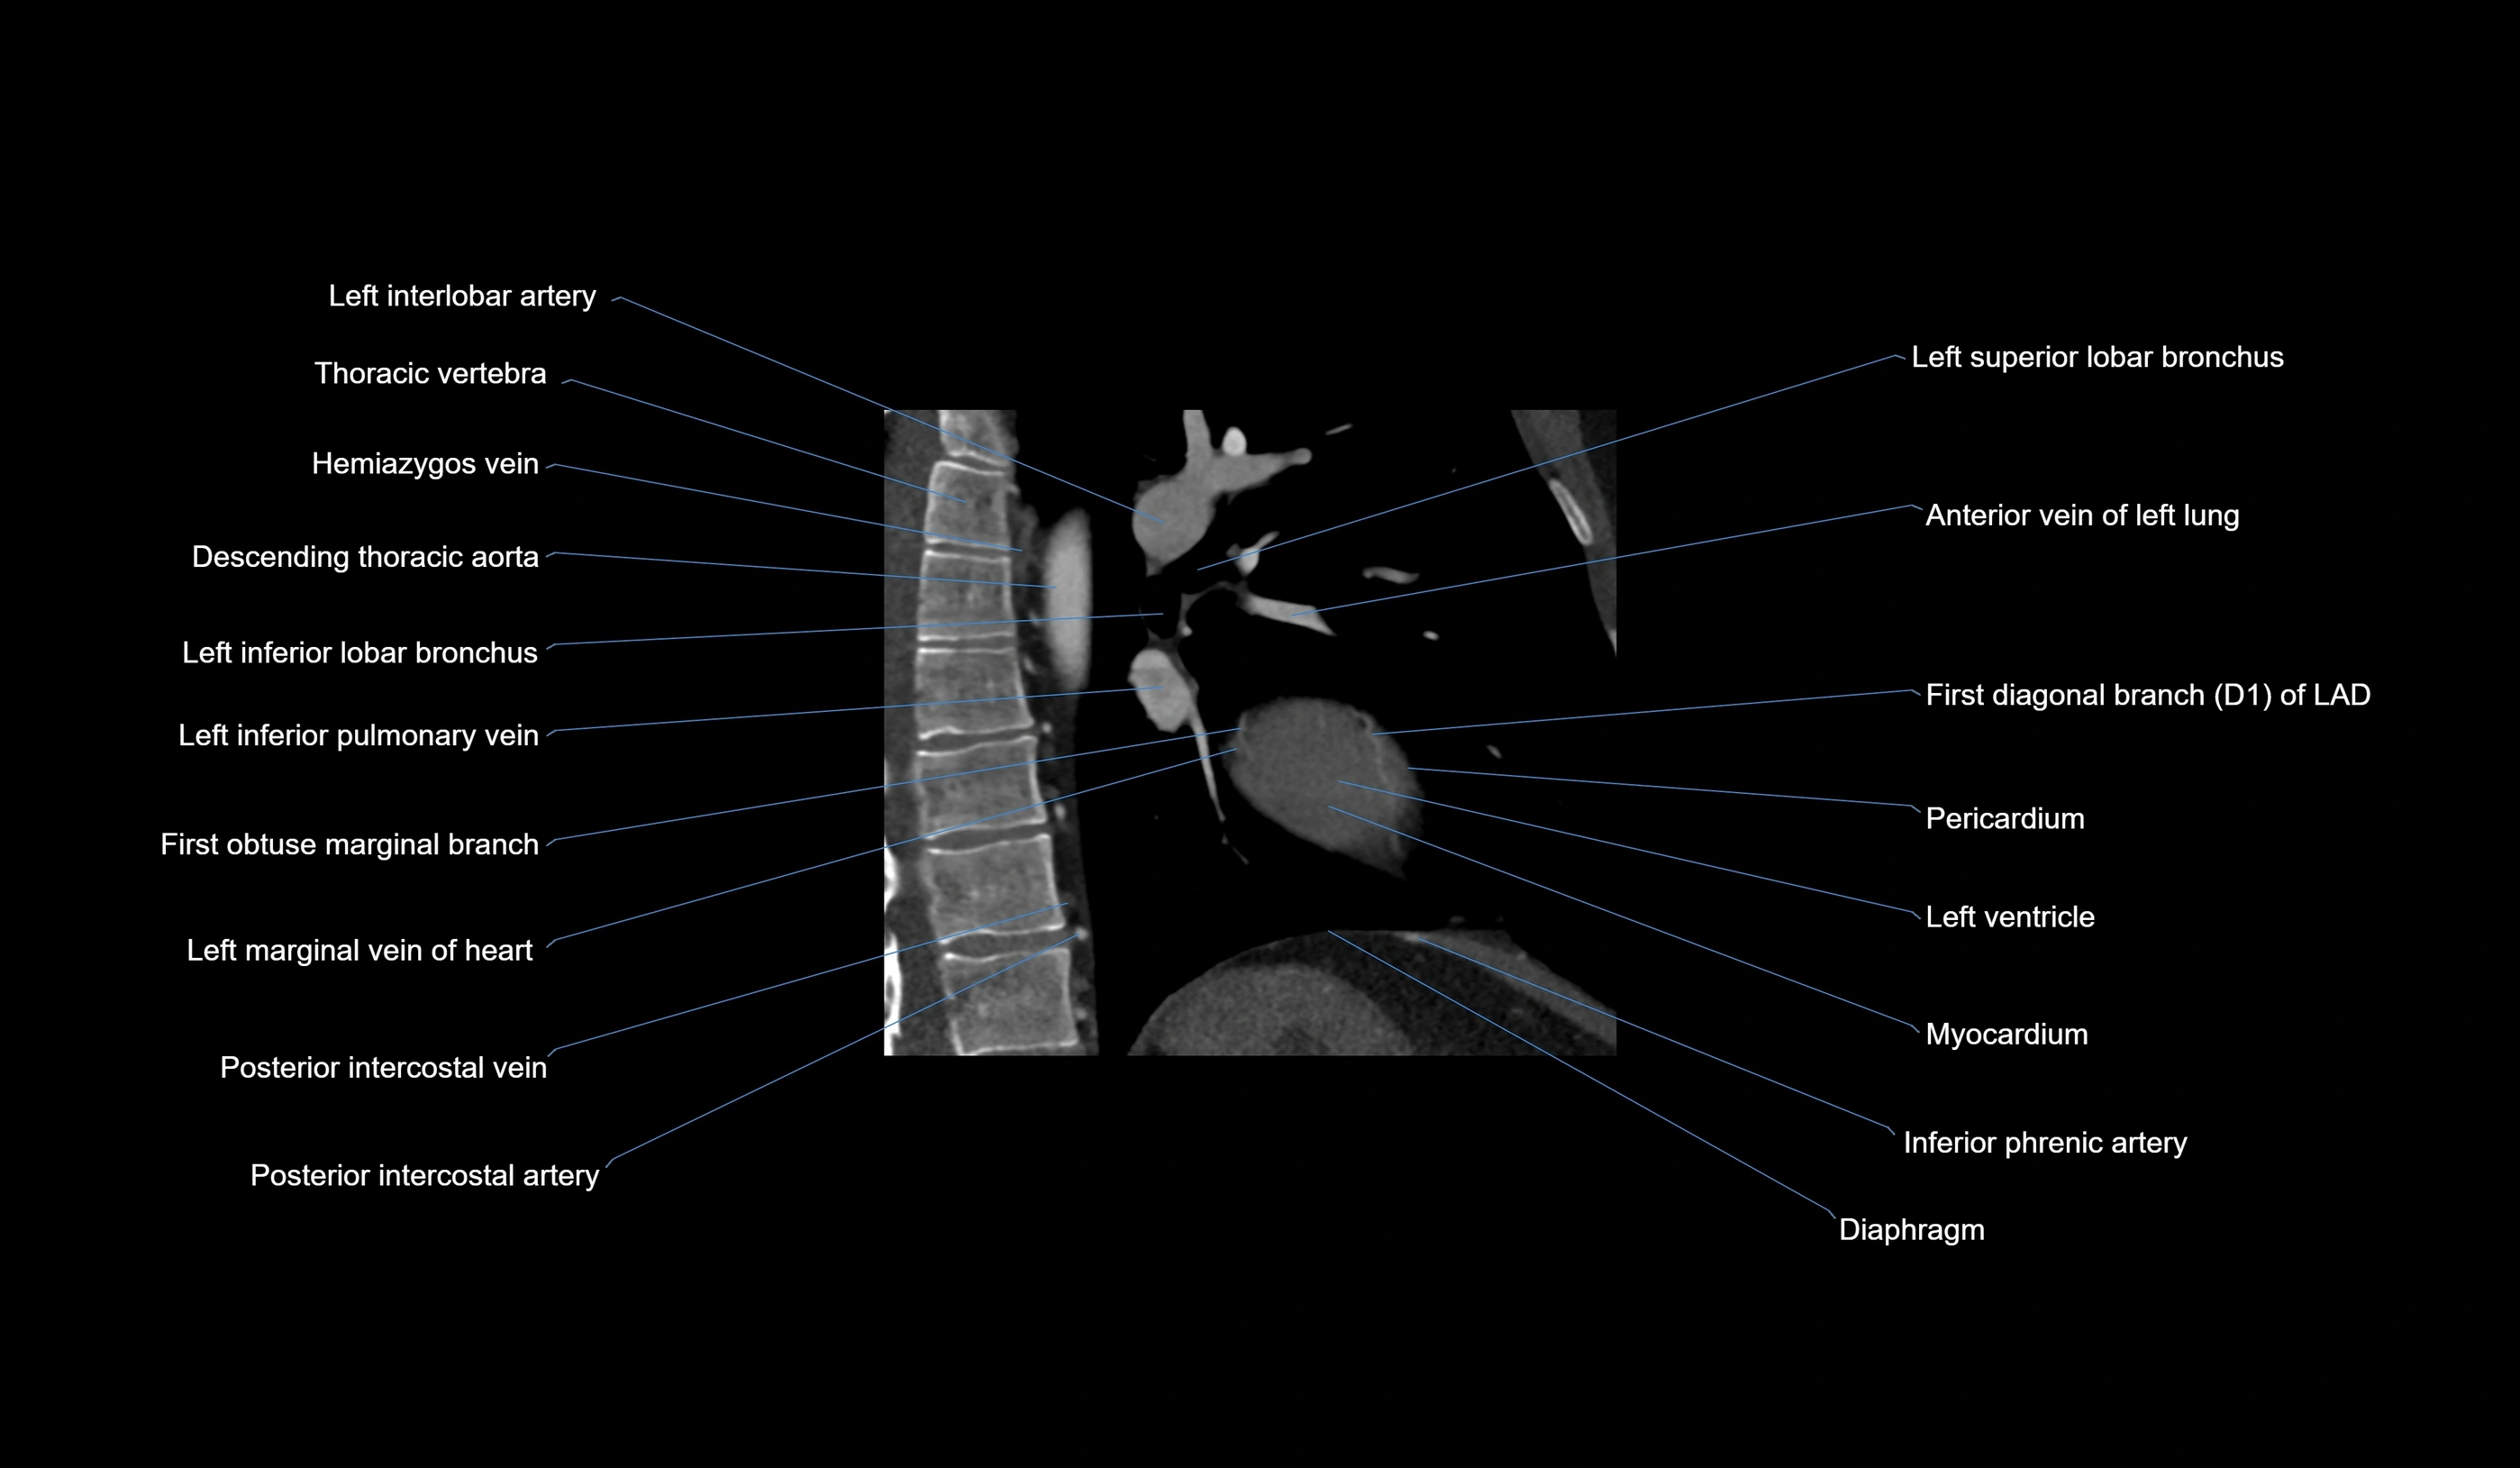

- Descending thoracic aorta

- Left inferior lobar bronchus

- Left inferior pulmonary vein

- Left interlobar artery

- Left superior lobar bronchus

- First diagonal branch (D1) of LAD

- First obtuse marginal branch

- Inferior phrenic artery

- Left marginal vein

- Posterior intercostal arteries

- Posterior intercostal veins